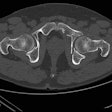

- Malignant bone disease (2.4%)

Indeterminate lesion on PET/CT classified by PET/MRI for 53-year-old man with lung cancer. Contrast-enhanced CT (A), PET (B), and fused F-18 FDG PET/CT (C) images are displayed in comparison with contrast-enhanced T1-weighted MRI (D), PET (E), and fused F-18 FDG PET/MRI (F) images. In CT (A), hyperdense, subcentimeter liver lesion (arrows) in segment VII is suggestive of transient hepatic attenuation difference or small hemangioma. As malignancy cannot be excluded, it needs further investigation. On PET/MRI, lesion is clearly classified as metastasis because of contrast enhancement and tracer uptake due to later acquisition time point. Follow-up CT confirmed diagnosis after 78 days. Image courtesy of the Journal of Nuclear Medicine.

Indeterminate lesion on PET/CT classified by PET/MRI for 53-year-old man with lung cancer. Contrast-enhanced CT (A), PET (B), and fused F-18 FDG PET/CT (C) images are displayed in comparison with contrast-enhanced T1-weighted MRI (D), PET (E), and fused F-18 FDG PET/MRI (F) images. In CT (A), hyperdense, subcentimeter liver lesion (arrows) in segment VII is suggestive of transient hepatic attenuation difference or small hemangioma. As malignancy cannot be excluded, it needs further investigation. On PET/MRI, lesion is clearly classified as metastasis because of contrast enhancement and tracer uptake due to later acquisition time point. Follow-up CT confirmed diagnosis after 78 days. Image courtesy of the Journal of Nuclear Medicine.After exclusions, the researchers examined 1,003 PET/MRI scans of 918 patients. PET/MRI outperformed PET/CT in terms of providing more tumor information (26.3%), mostly in patients with malignant bone disease, followed by lung cancer, prostate cancer, and gynecologic or breast cancer. PET/MRI identified additional malignant findings in 5.3% of cases, which lead to a change in tumor, node, and metastases (TNM) staging in 2.9% of cases. PET/MRI also clearly classified indeterminate PET/CT lesions in 11% of cases.